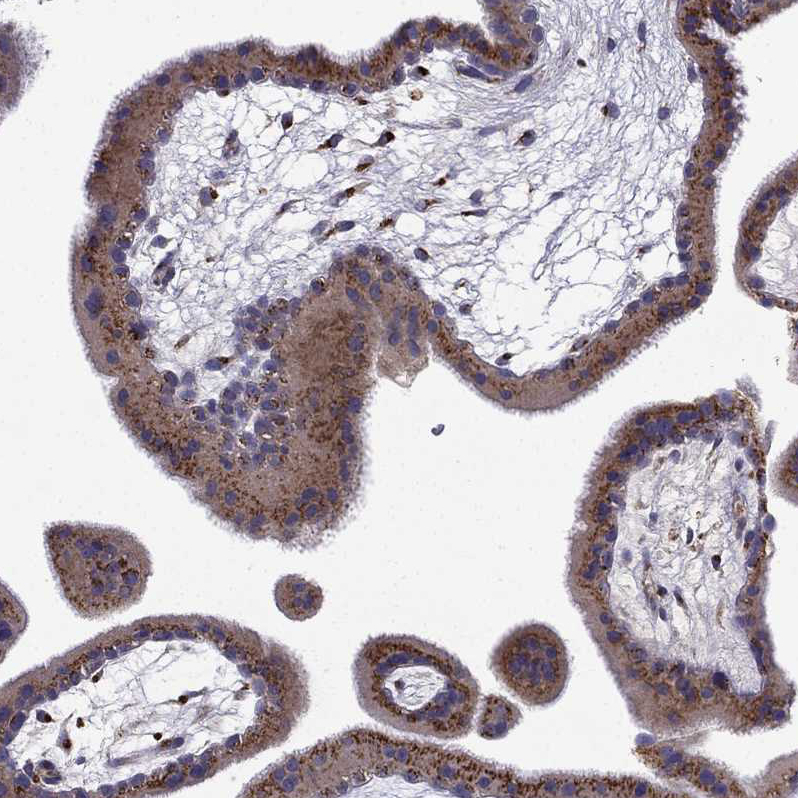

Immunohistochemical staining of human placenta shows moderate granular cytoplasmic positivity in trophoblastic cells.